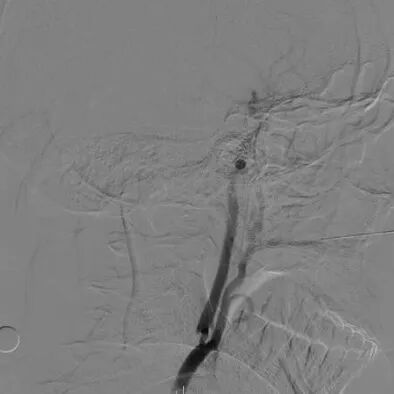

心脑联合造影

-- 右侧颈内起始部中度狭窄,经前交通向左侧代偿